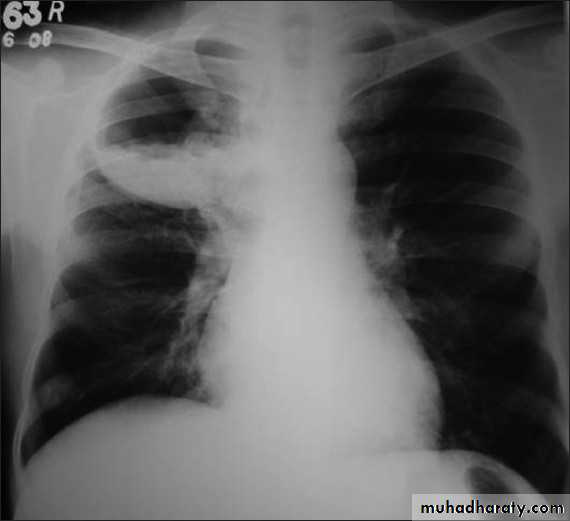

Pleural effusion

50.pleural effusion

51.pleural effusion .